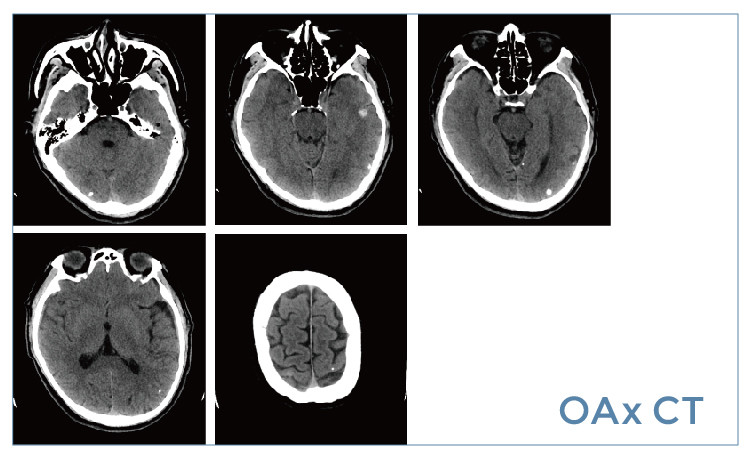

【朗润影像档案】20190524磁共振影像病例结果讨论

【朗润影像档案】磁共振影像病例分享(编号20190524)